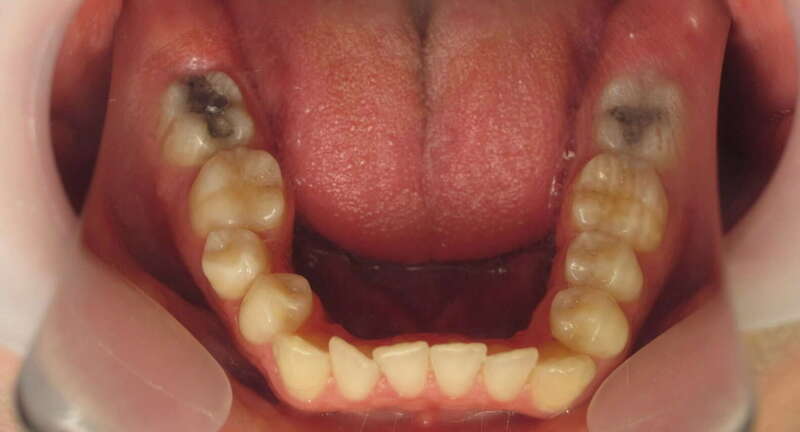

Cas n°9 traité par multi-attaches - adolescent

Ce cas d'adolescent illustre une stratégie de développement d'arcade réussie. Le patient présentait un encombrement massif et des inversions d'articulé rendant l'occlusion instable.

Le traitement a été réalisé avec des multibagues autoligaturantes, choisies pour leur capacité à générer des forces légères et continues, idéales pour l'expansion transversale. Cette approche a permis de corriger l'encombrement et les inversions d'articulé sans extractions dentaires, en remodelant simplement la forme des arcades.

Résultats clés :

• Transformation d'arcade : Passage d'une arcade étroite et encombrée à une arcade large et fonctionnelle.

• Occlusion optimale : Rétablissement d'un engrènement sain, protégeant les dents contre les usures anormales.

• Esthétique naturelle : Le sourire est élargi, harmonieux et parfaitement intégré au profil du patient.

C'est une démonstration de l'efficacité biologique de l'orthodontie moderne, qui privilégie la conservation dentaire et le respect des structures osseuses.